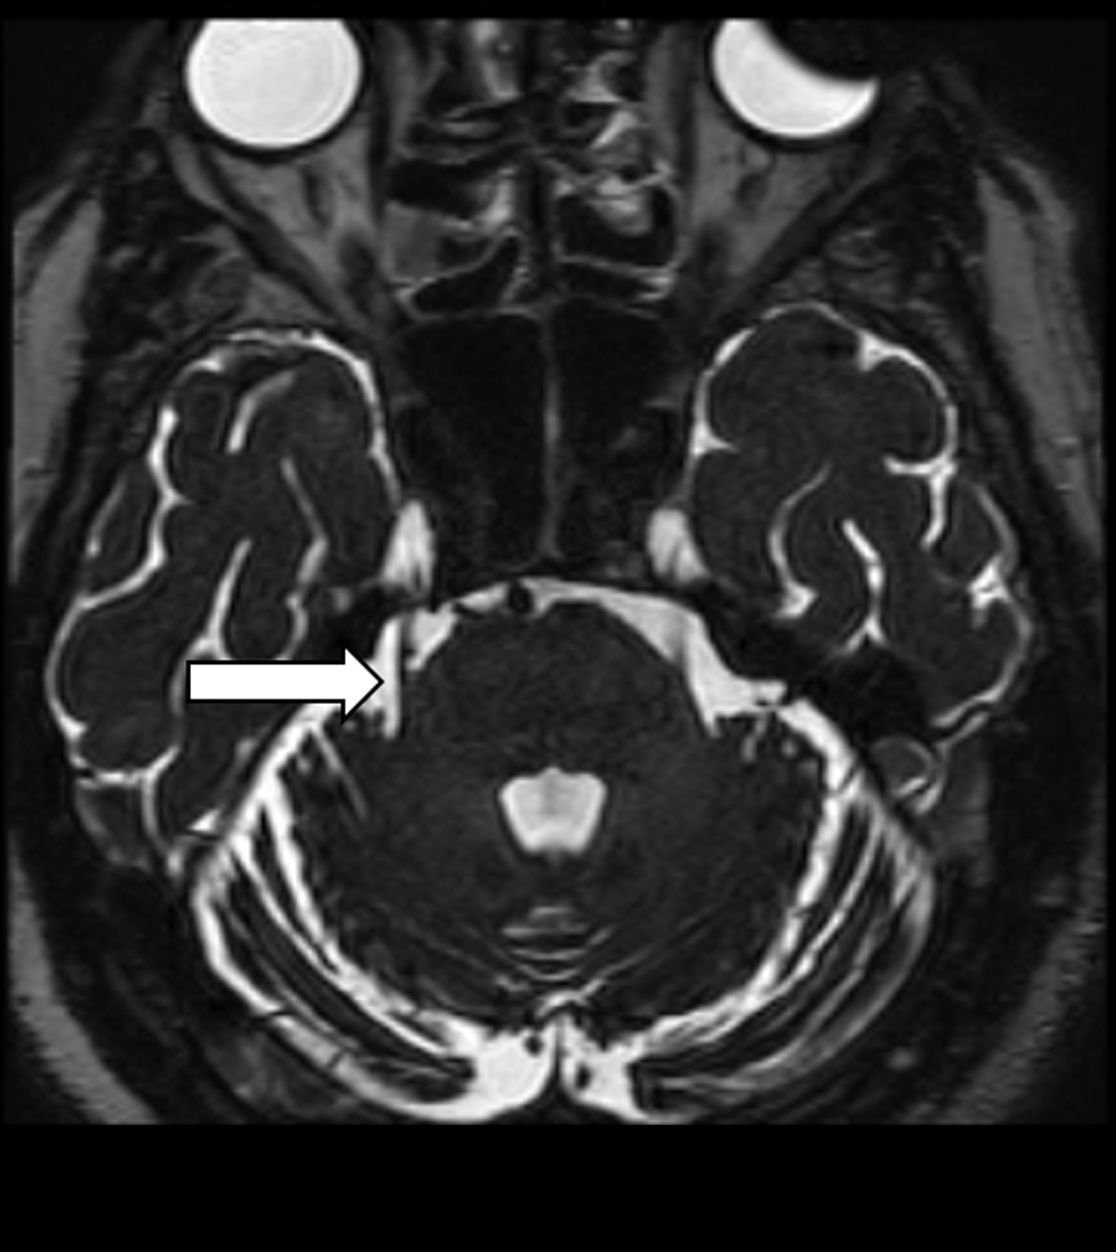

Im Nervenwasserraum (Liquor) einliegender Schlauch zur intrathekalen Therapie (Pfeil)